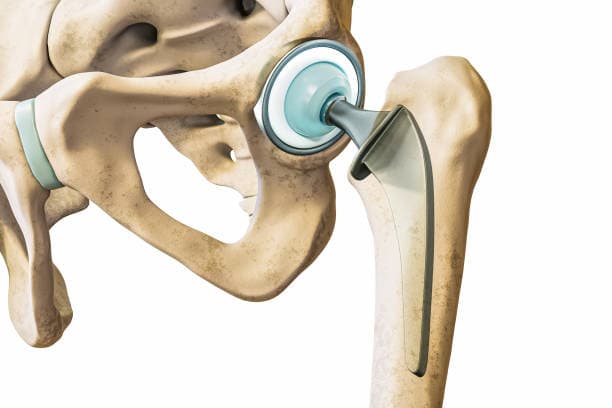

The surgical procedure involves making an incision over the hip, through which the surgeon accesses the joint. The damaged femoral head is removed and replaced with a metal or ceramic ball attached to a stem that fits into the femur. The acetabulum is also prepared by removing any damaged cartilage and bone, then resurfaced with a metal or plastic cup. These prosthetic components are designed to mimic the natural anatomy and movement of the hip joint, allowing for smooth articulation and reduced pain.

Implant Placement: The prepared bone surfaces are fitted with the prosthetic components. The femoral component, which includes a metal stem and a ball, is inserted into the femur. This can be cemented in place or designed to allow bone growth into the implant. The acetabular component, typically a metal shell with a plastic or ceramic liner, is placed into the prepared socket. These components are aligned to ensure proper joint movement and stability.